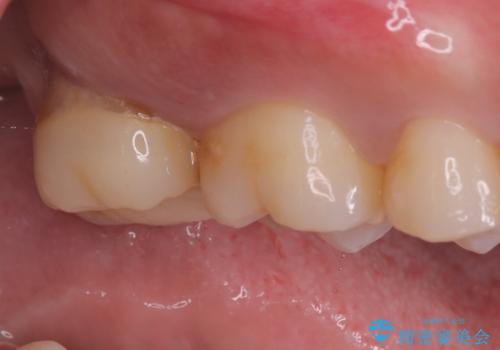

- 海外に転居する前に治療を完了させたいと来院された患者様です。

根管治療からセラミッククラウンまで来院回数は5回で治療を完了することができました。

治療前は遠心のポケットが7mmほどありましたが、治療後には3mmに改善しています。